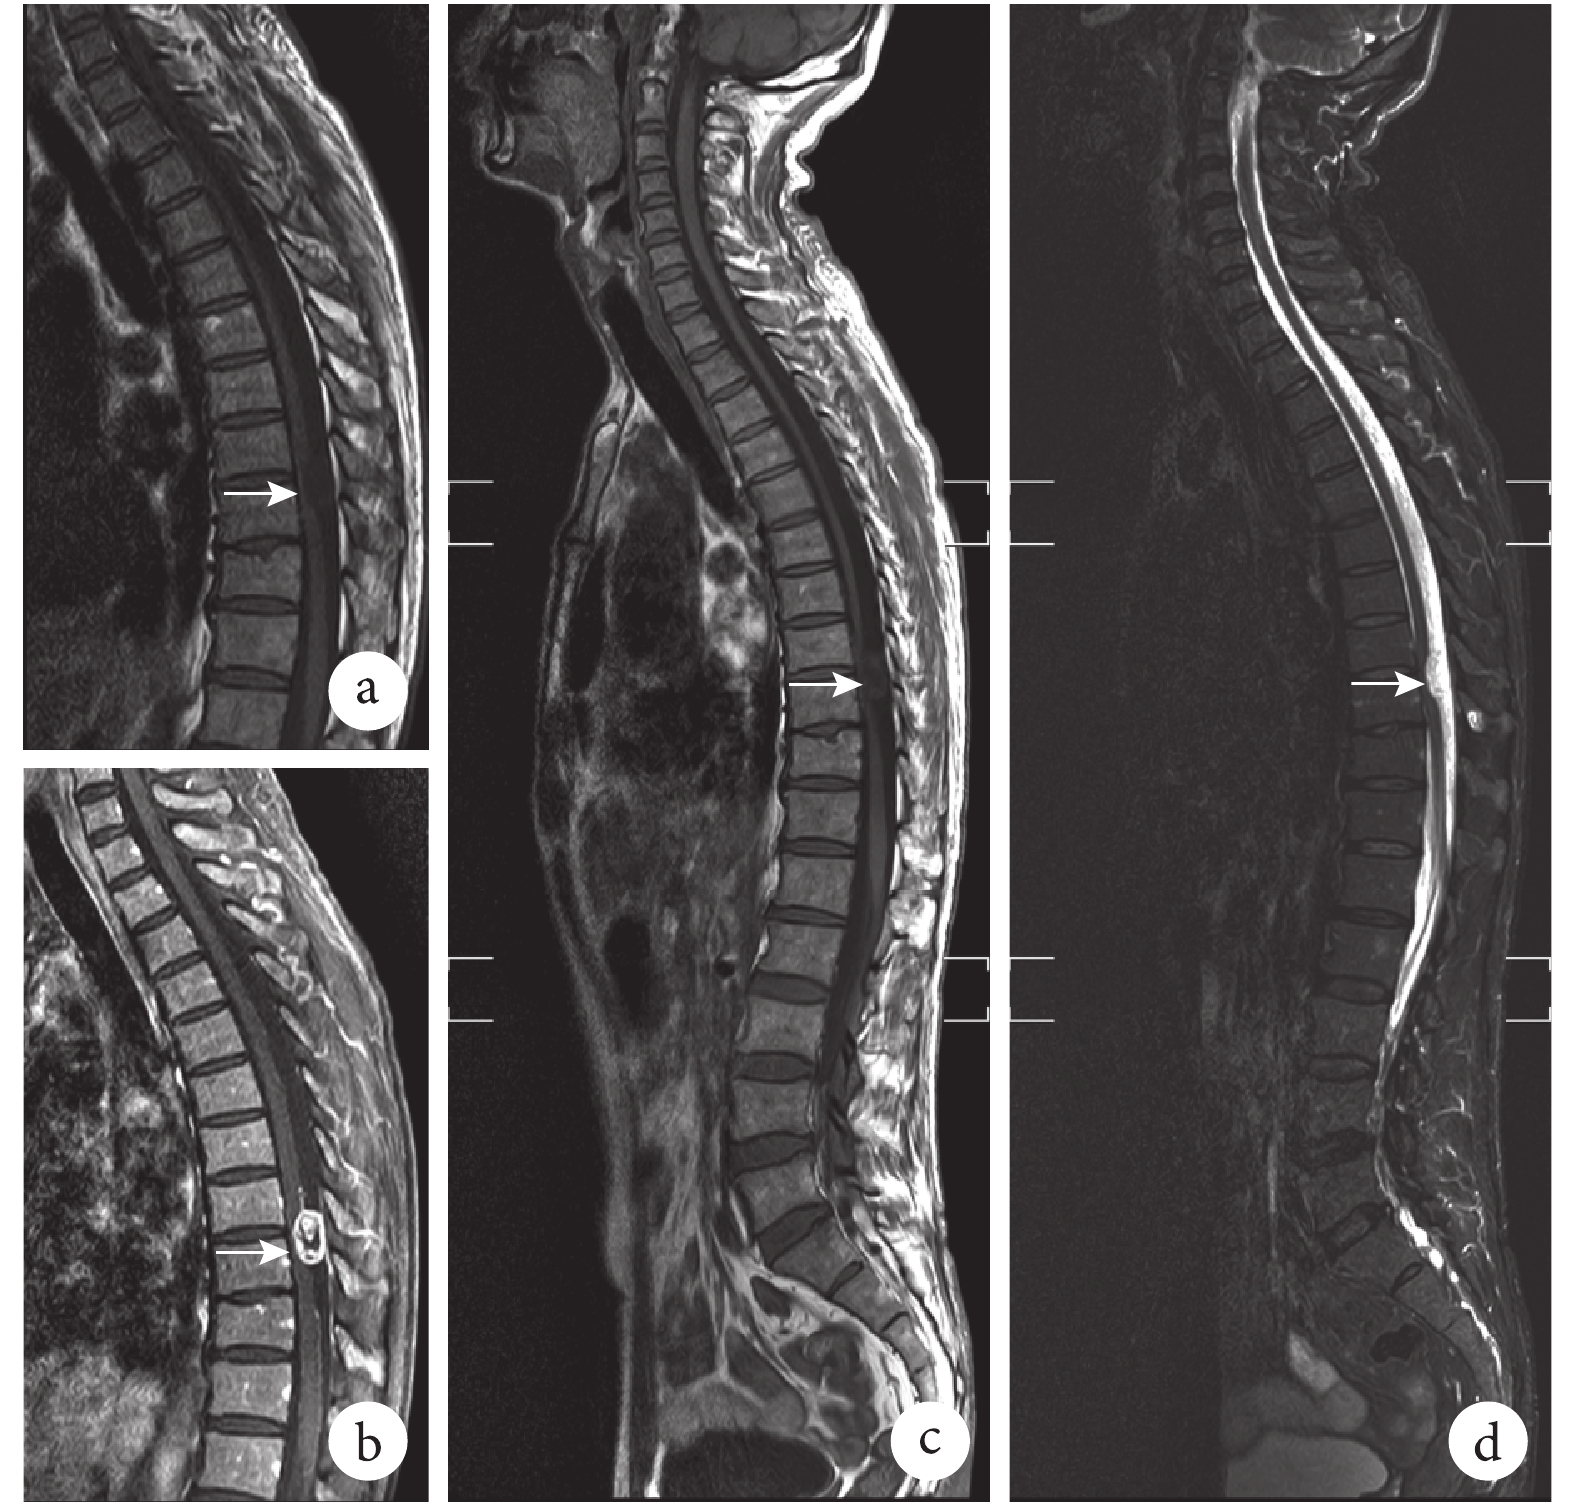

② 脊柱及椎管內多發病變。患者 2,男,54 歲。因“腰部疼痛伴雙下肢麻木 5+ 個月”入院。體格檢查:腰背部叩痛陽性。單一的腰椎 MRI 平掃只能發現腰 2 椎體平面的硬脊膜下占位,而 WSMRI 發現胸 9、腰 2 椎體平面各有 1 個硬脊膜下占位,且伴有頸 6/7、腰 4/5、腰 5/骶 1 椎間盤膨出。予以一次手術同時切除腰 2 及胸 9 椎體平面兩處病變,術后病理證實均為神經鞘瘤。見圖 2。

a、b. 腰椎 MRI 平掃提示腰 2 椎體平面椎管內髓外硬膜下占位性病變(白箭),T1 像(a)長信號,T2 像(b)長、短信號;c、d. WSMRI 提示,除腰 2 椎體平面占位以外(白箭),尚有胸 9 椎體平面髓外硬膜下占位(白箭頭),兩處病變均為 T1 像(c)長信號,T2 像(d)長、短信號

脊柱及椎管內常有多發病變,如脊柱轉移瘤、多發神經鞘瘤等,亦常合并脊柱側彎、嚴重椎體血管瘤等可能影響術后脊柱穩定的病變[3, 10-11]。WSMRI 可全面、直觀、立體發現多個病灶,如 18 例陽性患者中的多例椎體與椎間盤多發病變,有助于術前全面的診斷,避免漏診、誤診及術后可能出現的不明原因的病情加重,減少醫患糾紛。為臨床提供了重要的影像資料,有利于治療和手術方案的制定。如圖 2 所示,單一的腰椎 MRI 平掃只能發現腰 2 椎體平面的硬脊膜下占位,而 WSMRI 發現 T9、L2 椎體平面各有1個硬脊膜下占位,且有頸 6/7、腰 4/5、腰 5/骶 1 椎間盤膨出。予以一次手術同時切除 2 處病變,避免了漏診及潛在的醫療糾紛。